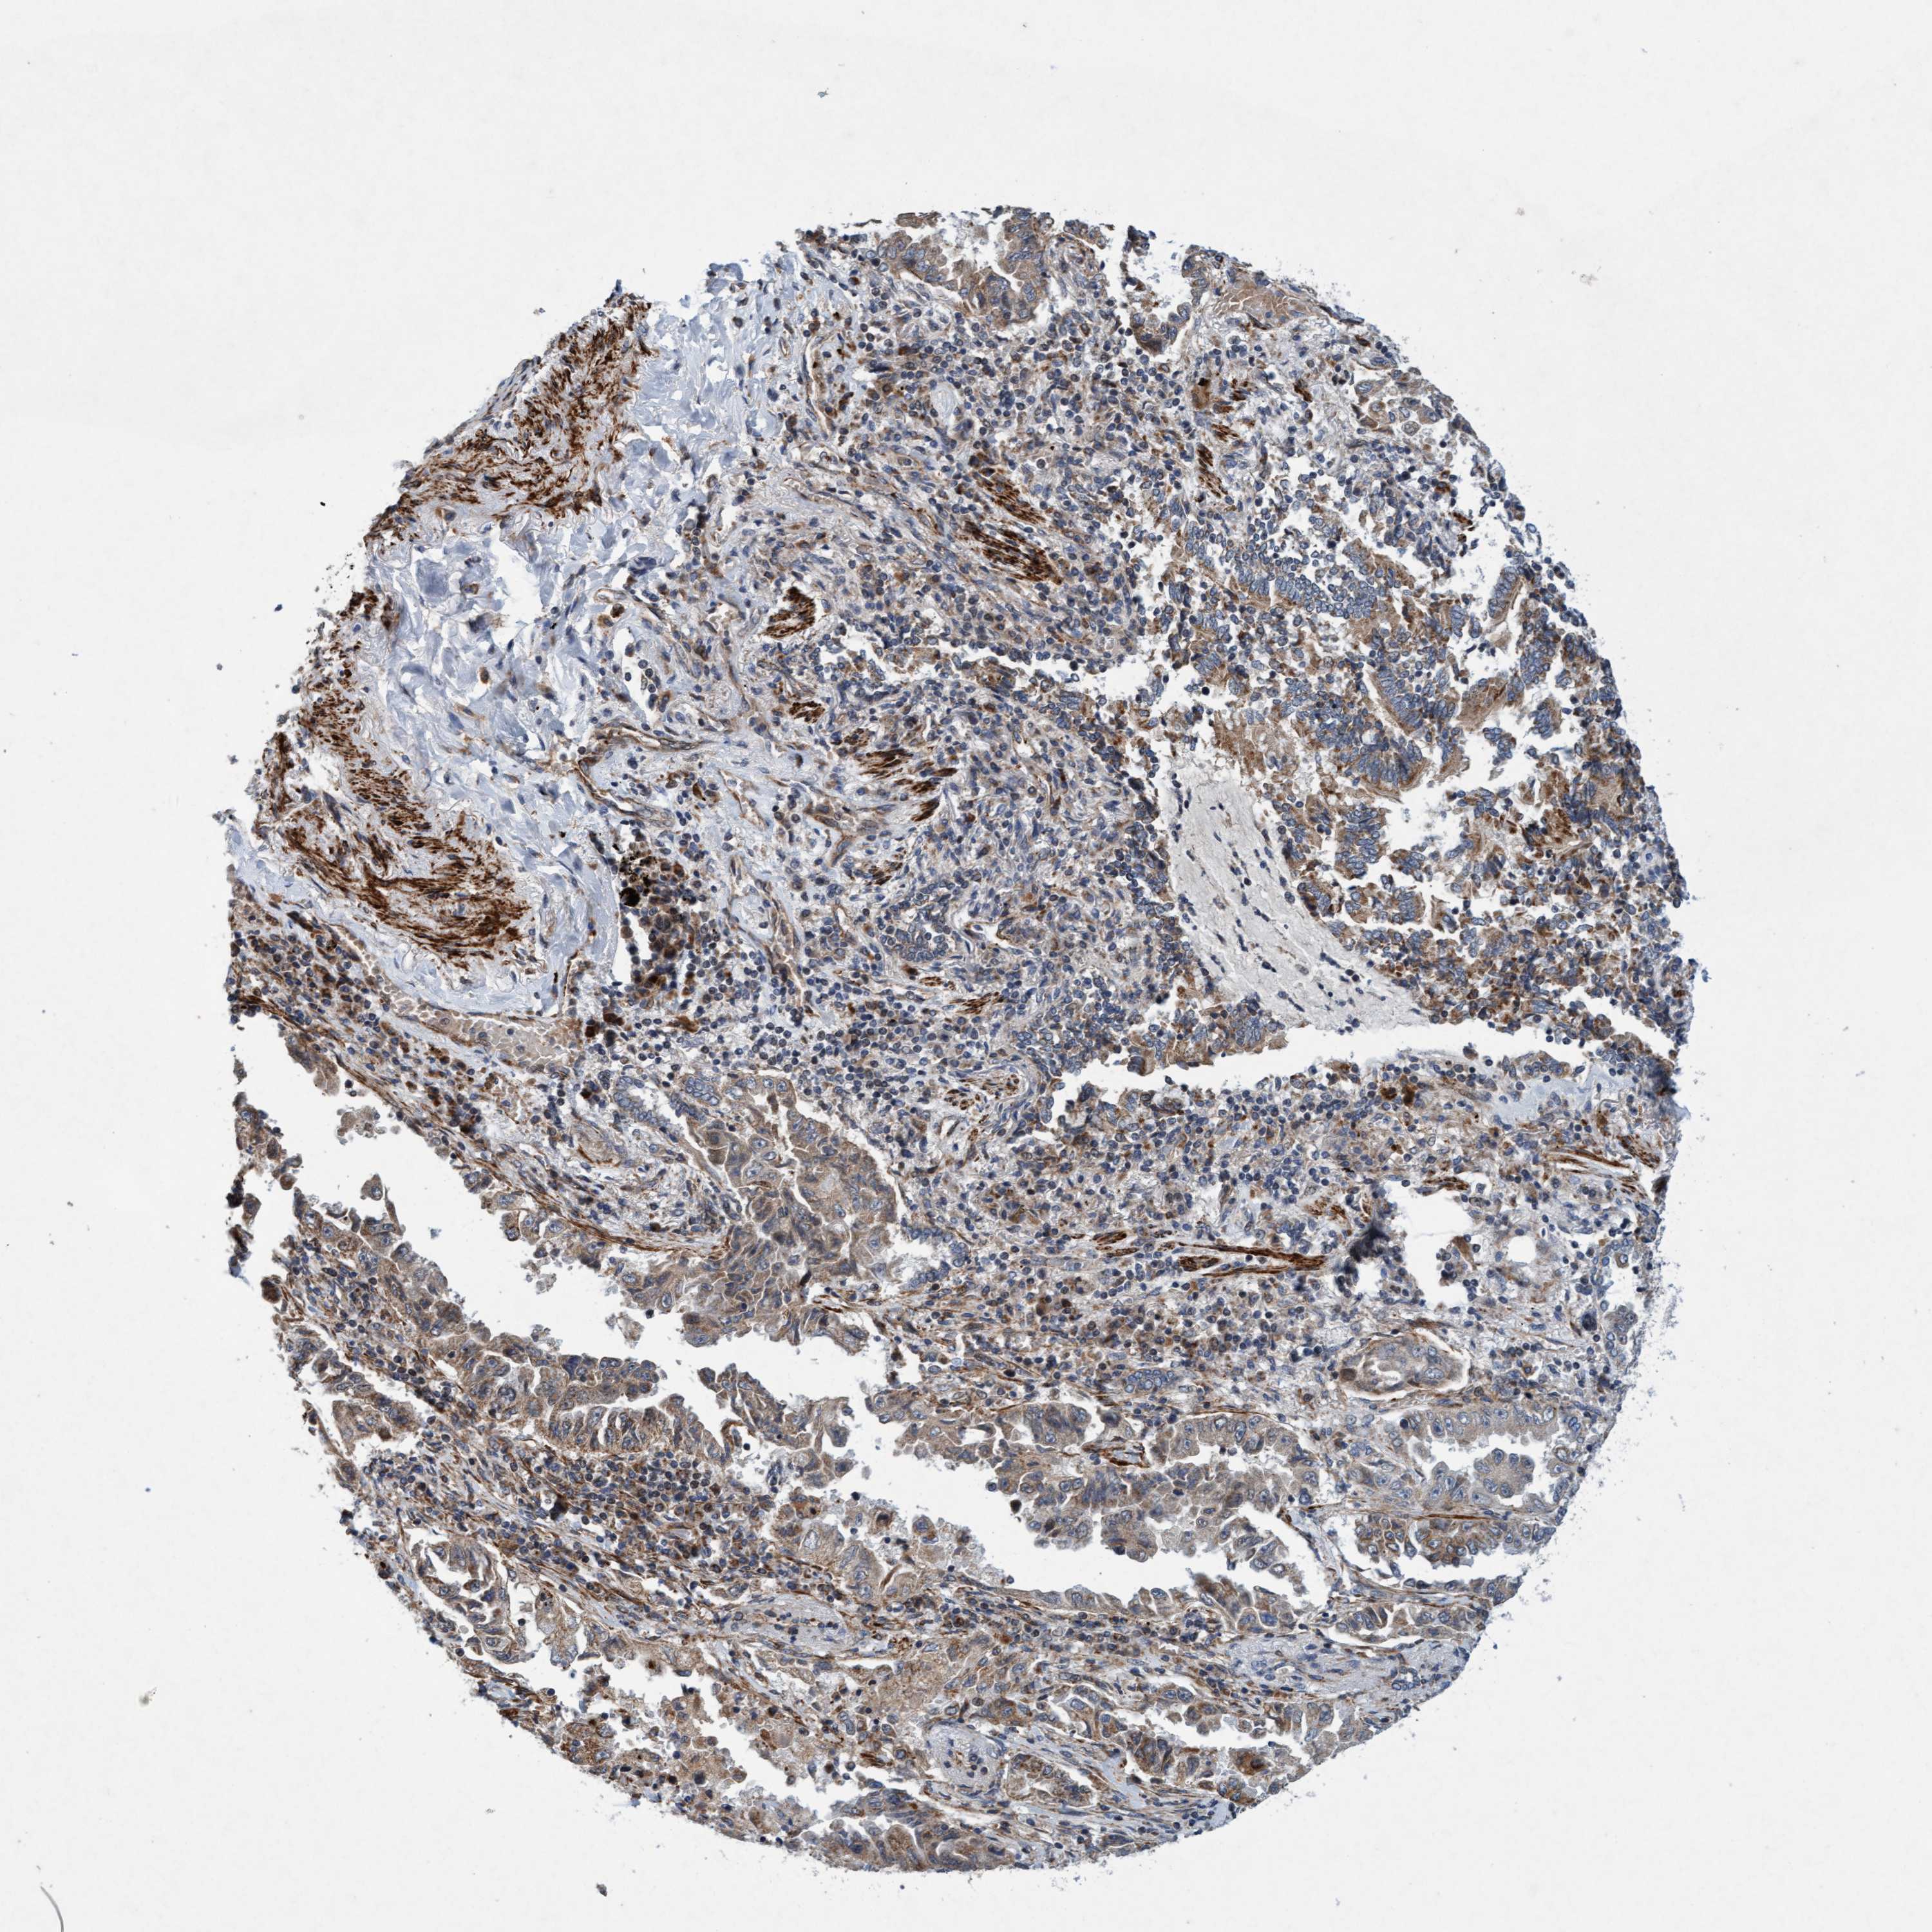

CANCER LUNG CANCER Show tissue menu

LUAD TCGA LUAD VALIDATION LUSC TCGA LUSC VALIDATION PROTEIN LUAD CPTAC PROTEIN LUSC CPTAC PROTEIN EXPRESSION